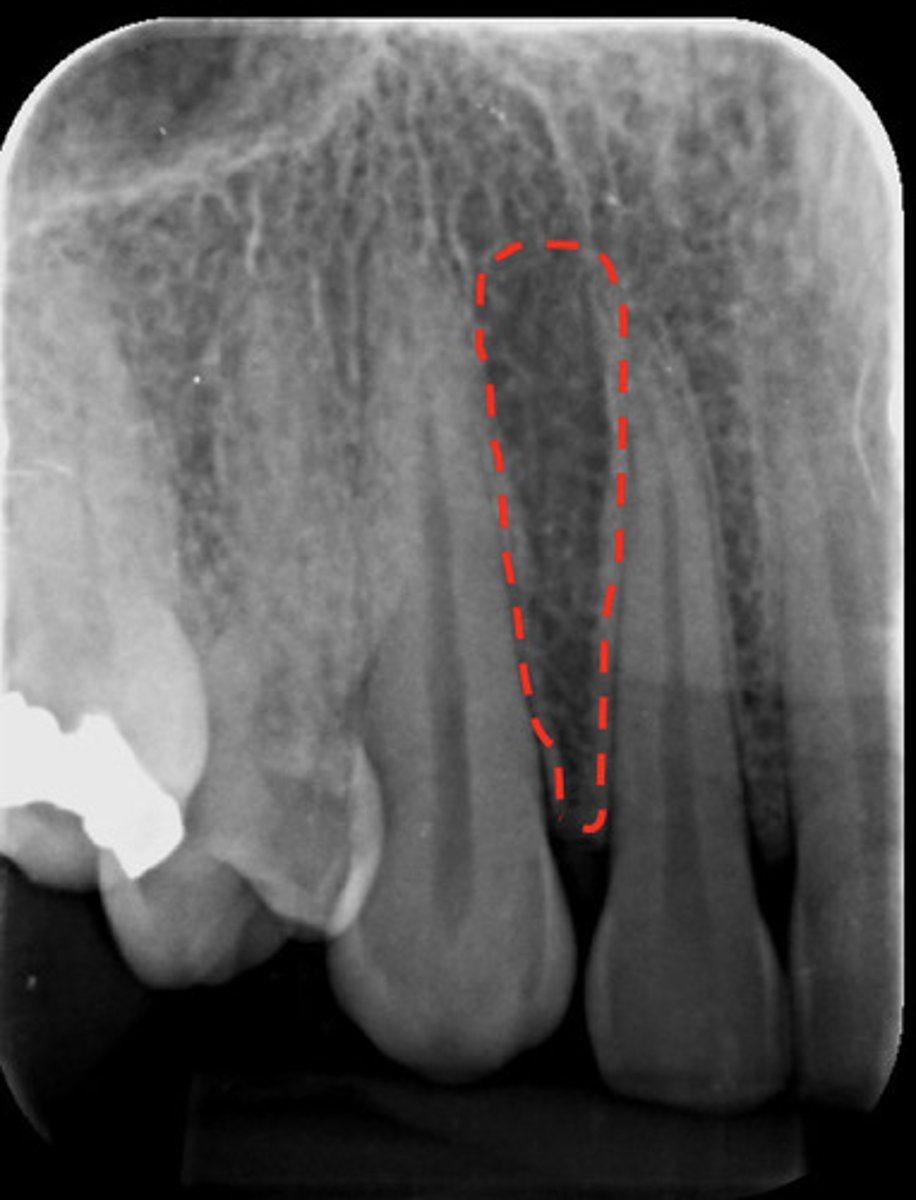

Nutrient canals

What are the red dotted lines representing?